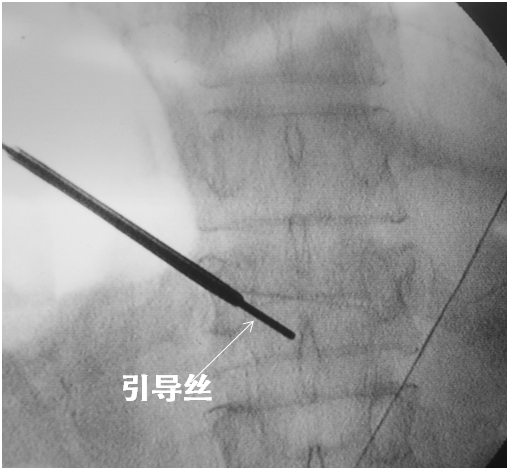

引导丝指引

取出针芯置入引导丝。

取出穿刺针外管沿引导丝放置工作通道:外鞘过椎体后缘3-5mm。